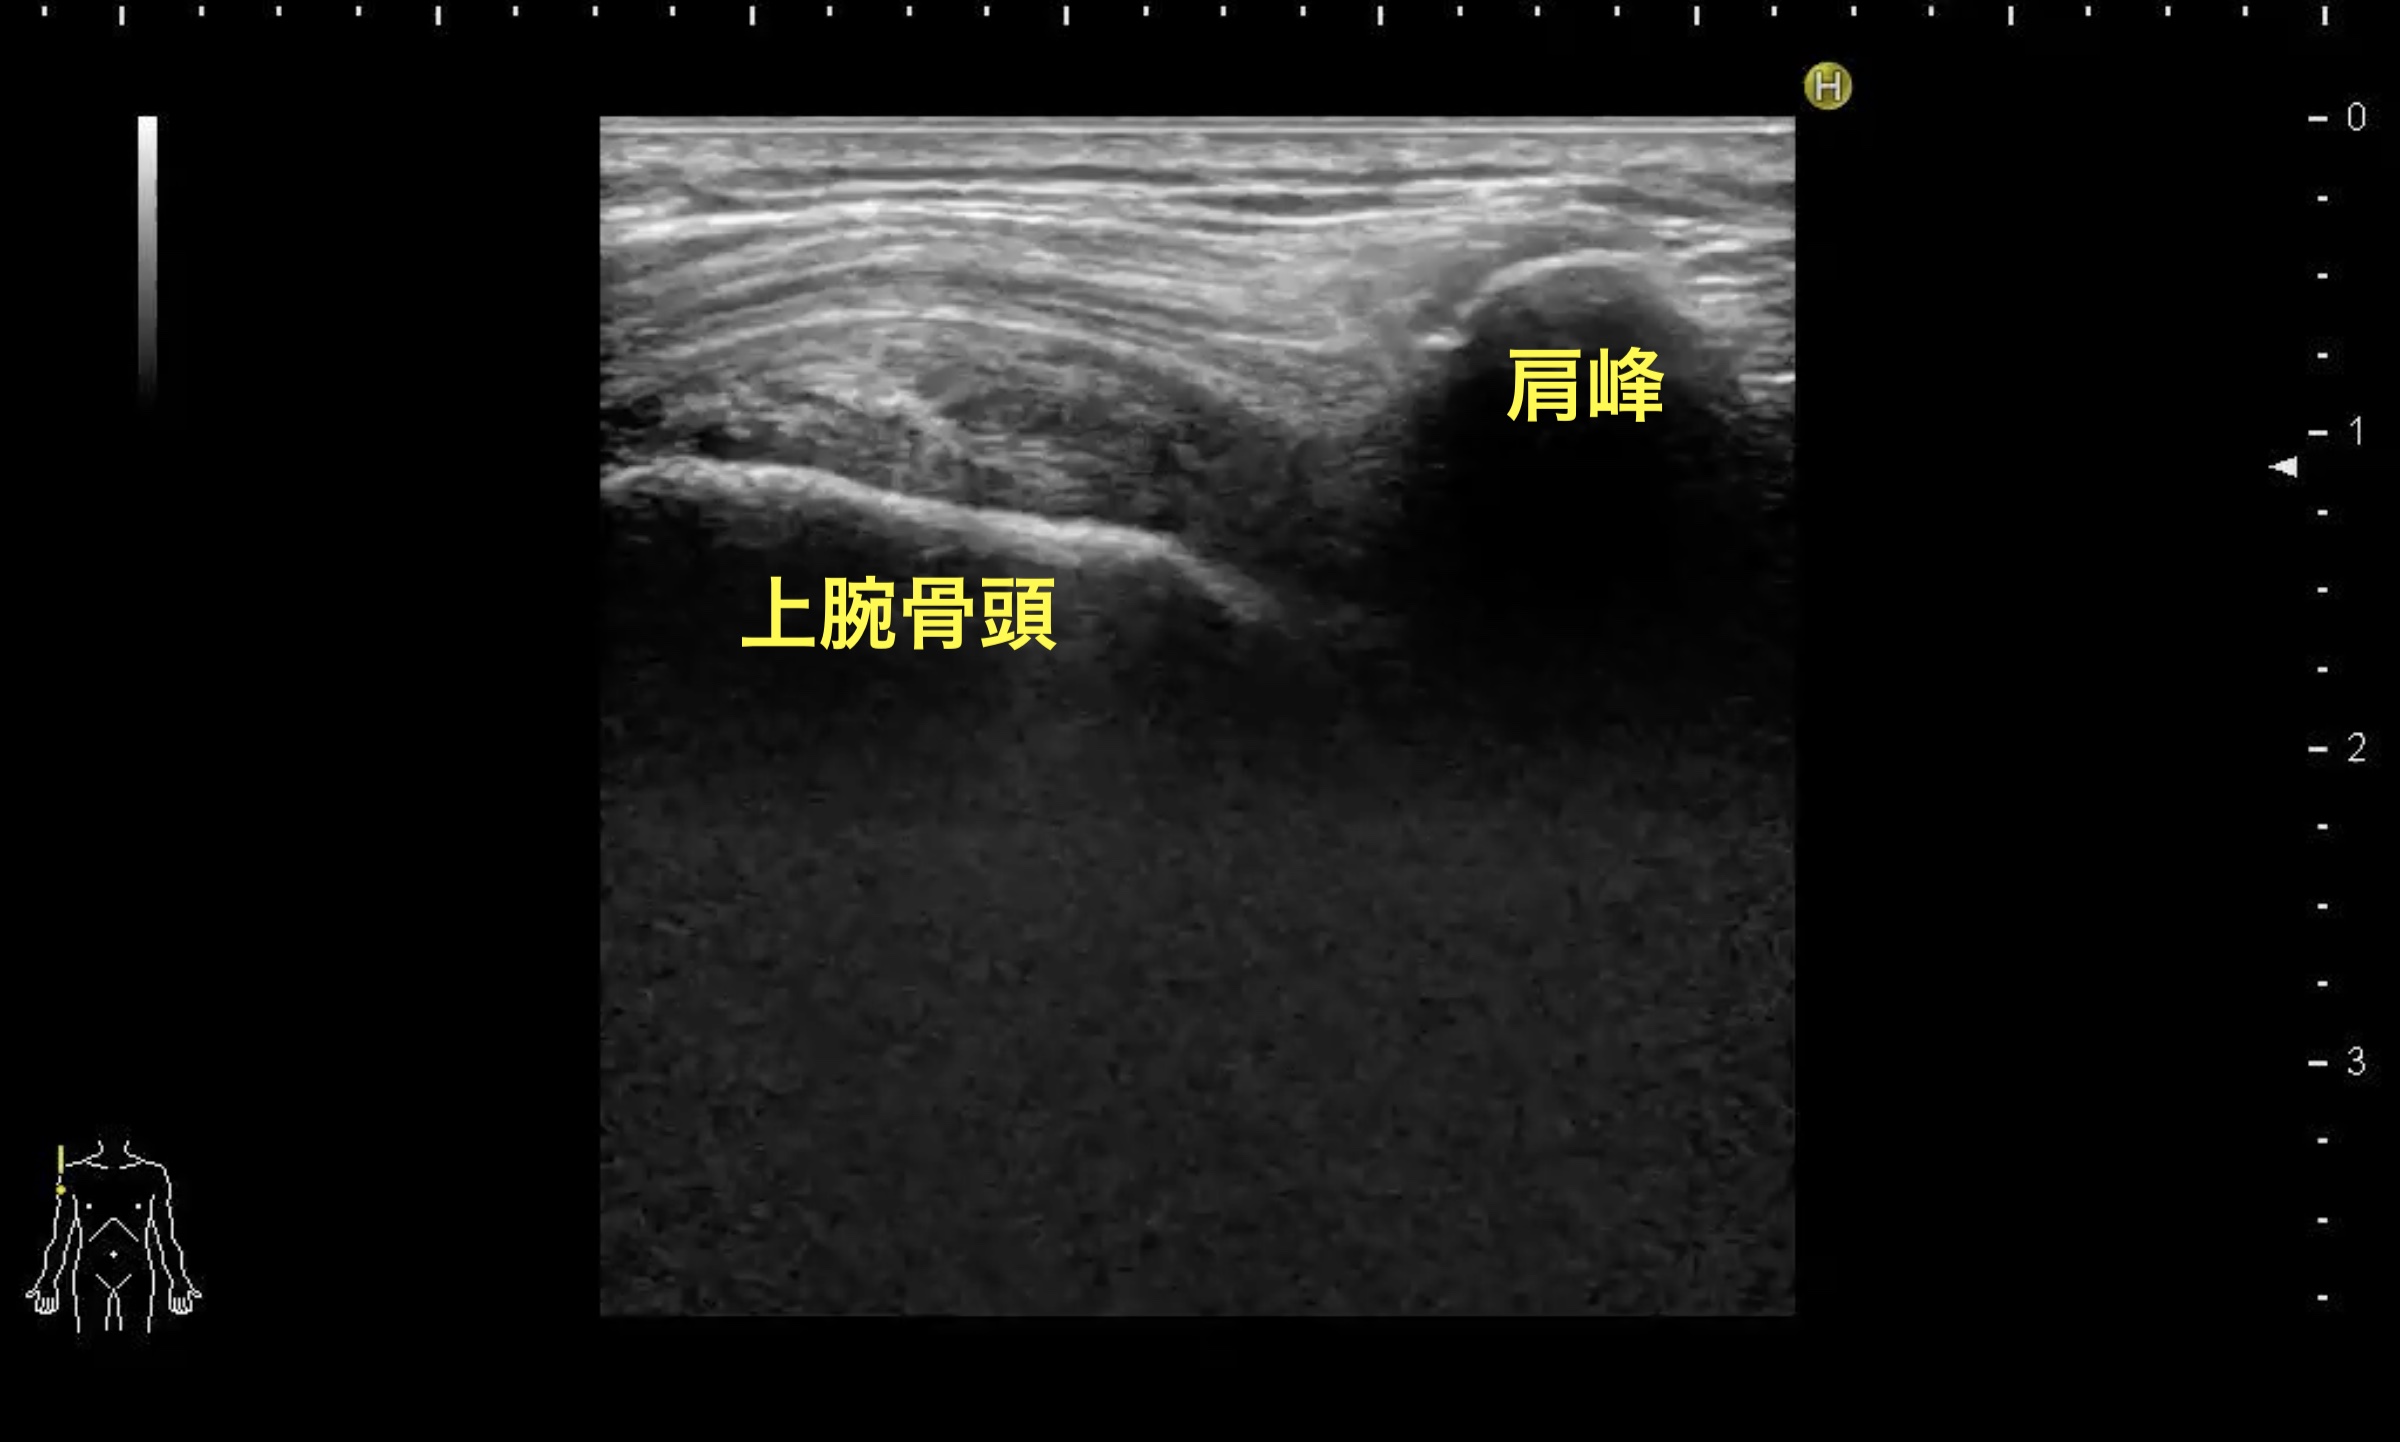

救急外来。左上腕打撲。考えられる疾患はなにか?

肩関節脱臼

肩関節脱臼に対する超音波検査の感度特異度は非常に高く、診断、除外ともに有用である。上の画像は肩関節外側からプローブを当てた際に得られる像で、左下図のように、正常では肩峰と遠位に隣接する上腕骨頭を同時に描出することができる。脱臼がある場合、右下図のように肩峰に隣接した上腕骨頭は消失し、三角筋が下に凸になるように同部位に移動する。レントゲンは合併する骨折も評価できるため極めて有用だが、体格などのため脱臼の有無が判別しにくい場合もあり、超音波を補助的に用いることで診断精度の上昇が期待できる。